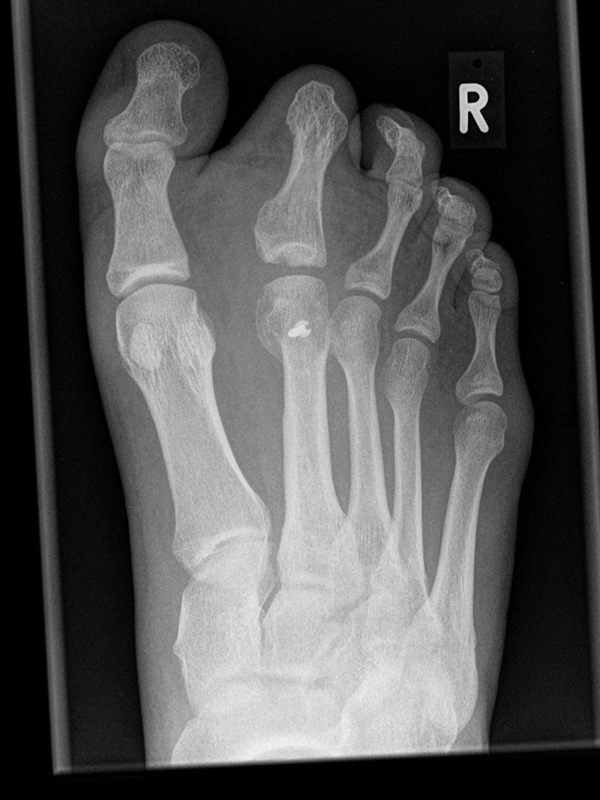

Fuß dp (dorsoplantar) mit Belastung

Kennzeichen des Röntgenbildes:

• Standardabbildung des Fußes zusammen mit der belasteten seitlichen Aufnahme und der unbelasteten Schrägaufnahme.

• Die belasteten Aufnahmen liefern relevante Informationen zur Fußstatik und sind die Grundlage aller achskorrigierenden Eingriffe an Vor- und Rückfuß.

• Sämtliche Winkelbestimmungen beziehen sich auf belastete Aufnahmen.

Besondere Bemerkungen zum Beispielbild:

• Schwere Hallux valgus Deformität.

• Die Sesambeine sind luxiert, ebenso das Großzehengrundgelenk. Luxation des Metatarsophalangealgelenks II.

• Degenerative Veränderungen der tarsometatarsalen (TMT) Gelenkreihe, betont TMT II und III.